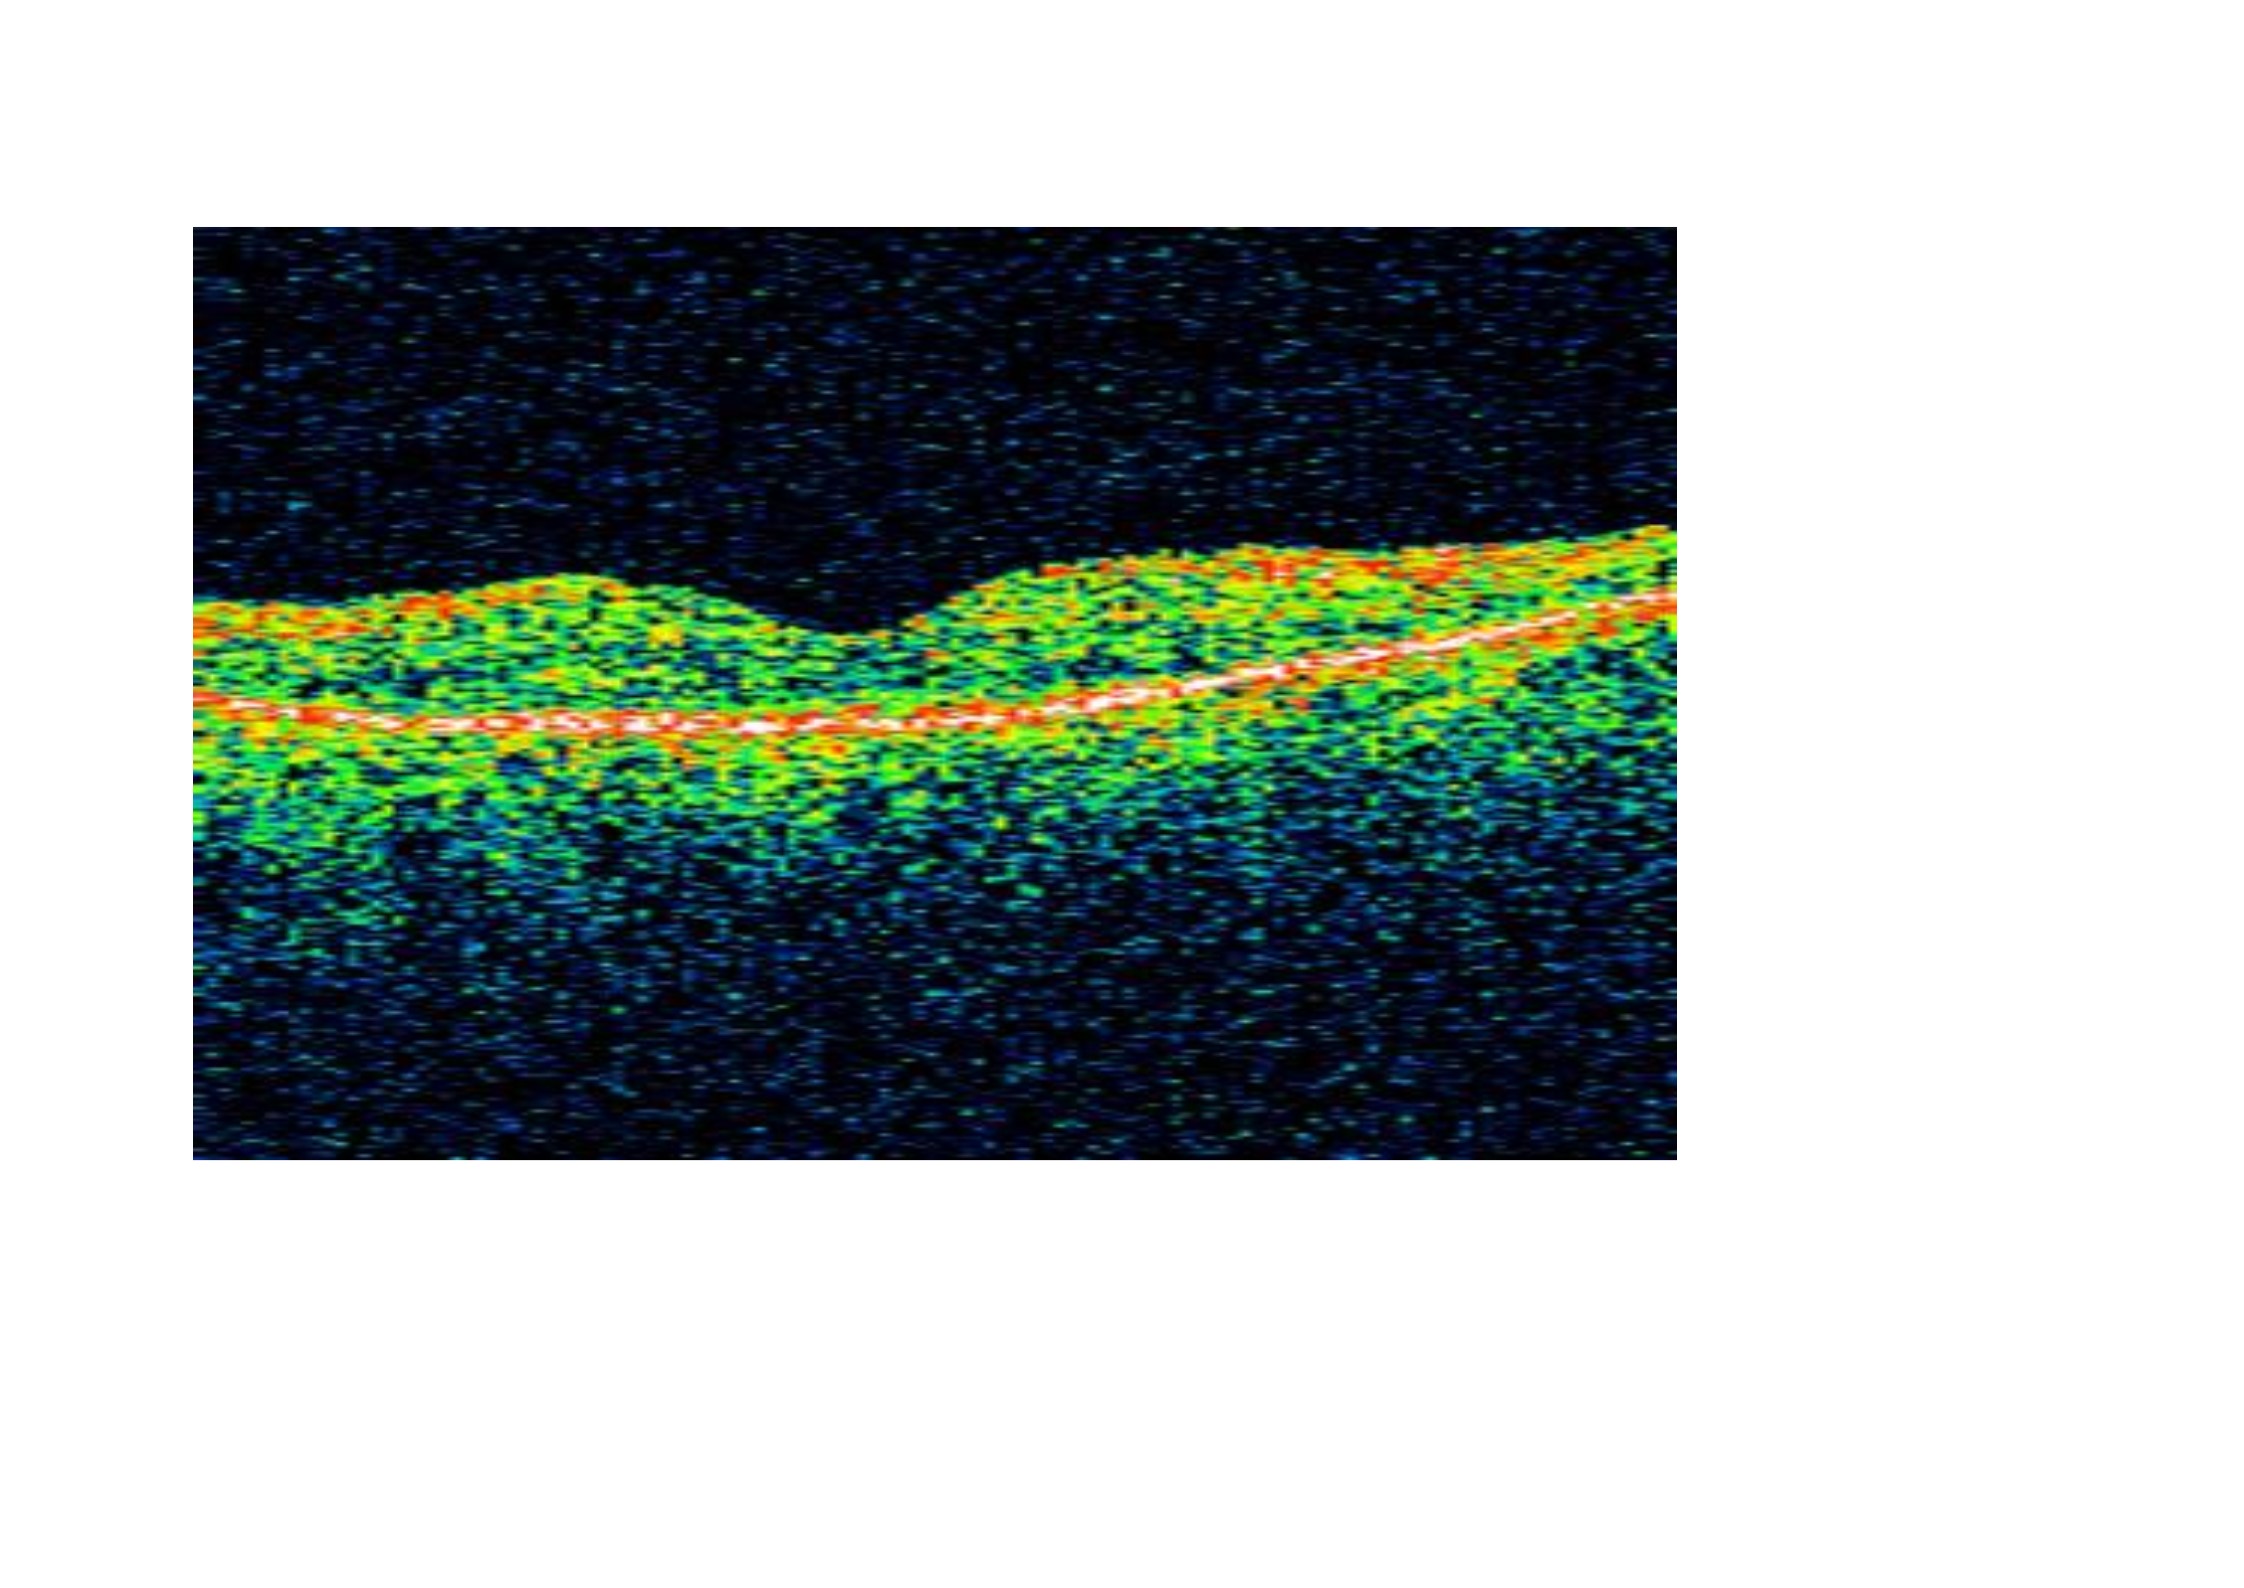

Con relativa frecuencia podemos encontrar edema macular cistoide en pacientes afectados de retinosis pigmentaria, causando pérdida visual central. Antes de la incorporación a la práctica clínica de la tomografía de coherencia óptica, muchos casos pasaban inadvertidos para los retinólogos. Nosostros sistemáticamente realizamos un cribado con OCT a estos pacientes para descartarlo. En numerosos casos hemos constatado una mejoría del edema macular tratando a estos pacientes con acetazolamida oral tal y como os mostramos en la OCT pre y post-tratamiento de un paciente atendido en nuestra clínica.